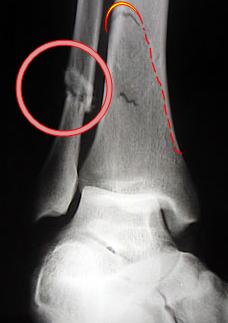

Distensió dels lligaments